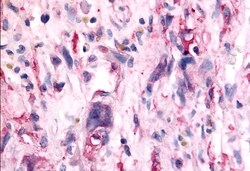

TAOK1 Polyclonal Antibody for IHC (P)

| Immunohistochemistry (Paraffin) | |